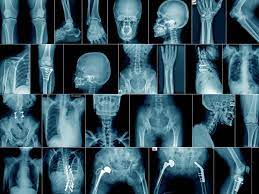

Nel dettaglio, dalle indagini sarebbe emersa l’esistenza di uno strutturato sodalizio criminale composto, tra gli altri, da un medico in servizio presso il pronto soccorso di un nosocomio cittadino, da un operatore socio sanitario (o.s.s.), da un soggetto titolare di un’agenzia di disbrigo pratiche automobilistiche, nonché da due “faccendieri” dediti all’organizzazione dei finti sinistri stradali. In particolare, il modus operandi accertato prevedeva la sistematica ripetizione di specifici accertamenti sanitari (radiografie), da parte dei medesimi soggetti che, di volta in volta, fornivano false e diverse generalità. A tal fine, soggetti con traumi e lesioni fisiche reali, procurati in contesti differenti (luoghi di lavoro, ambiente domestico o nell’esercizio di pratiche sportive), si presentavano con documenti d’identità riferiti a terze persone (le apparenti vittime dei falsi sinistri), presso il pronto soccorso dove, grazie alla complicità sempre dello stesso medico, ottenevano una corsia preferenziale (pochi minuti di attesa) e venivano avviati all’effettuazione di radiografie e degli esami specialistici, poi valorizzati per l’ottenimento degli indennizzi. Sono centinaia gli accertamenti oggetto di attenzione investigativa.